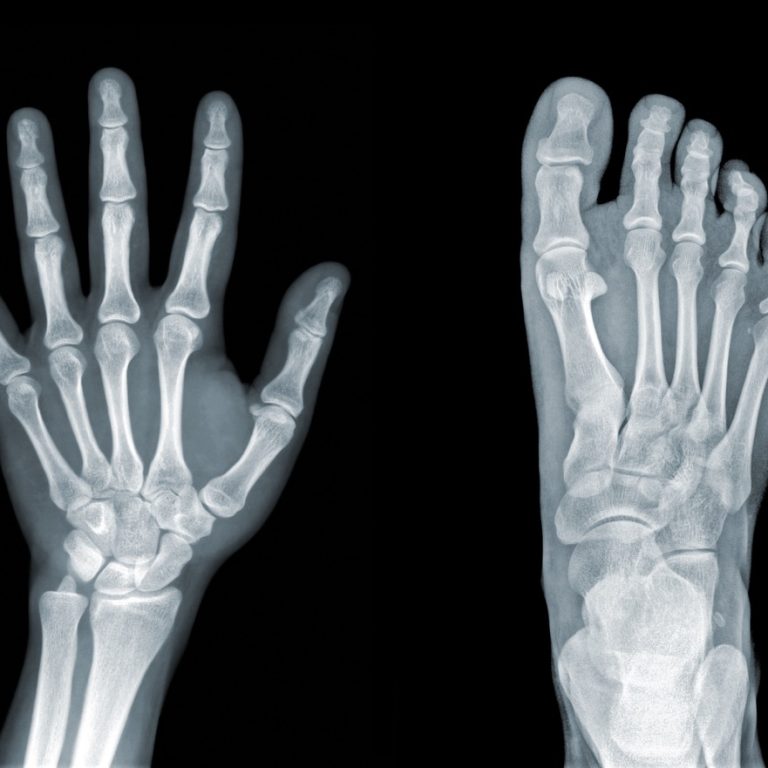

Ayak kireçlenmesinin nedenleri, destekleyici uygulamalar ve güncel tedavi yöntemleri detaylandırılmaktadır. Hareket özgürlüğünü artıran tıbbi çözümleri ve uzman önerilerini …

Parmakta kireçlenme sorununa dair tüm belirtileri, tıbbi tedavi yöntemlerini ve egzersiz uygulamalarını inceleyin. Uzman yaklaşımları ve cerrahi seçenekler …